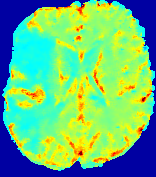

Slice #1Slice #2Slice #3Slice #4Slice #5Slice #6Dgtsuperscript𝐷gtD^{\text{gt}}Refer to captionRefer to captionRefer to captionRefer to captionRefer to captionRefer to caption(a)Refer to captionRefer to captionRefer to captionRefer to captionRefer to captionRefer to caption(b)Refer to captionRefer to captionRefer to captionRefer to captionRefer to captionRefer to caption(c)Refer to captionRefer to captionRefer to captionRefer to captionRefer to captionRefer to caption(d)Refer to captionRefer to captionRefer to captionRefer to captionRefer to captionRefer to caption(e)Refer to captionRefer to captionRefer to captionRefer to captionRefer to captionRefer to caption(f)Refer to captionRefer to captionRefer to captionRefer to captionRefer to captionRefer to captionRefer to caption000.060.060.060.120.120.120.180.180.180.240.240.240.300.300.30(mm2/s)𝑚superscript𝑚2𝑠(mm^{2}/s)

Figure 13: PIANO effectiveness and robustness testing: diffusion imaging via diffusion. Top row shows Dgtsuperscript𝐷gtD^{\text{gt}} used for simulating the ground truth pure diffusion. (a)-(f) refer to the results for D𝐷D estimated from the ground truth pure diffusion image time-series where Rician noise at levels 0%, 2%, 4%, 6%, 8%, 10% was added respectively.

Similarly, starting from the same initial condition C0superscript𝐶0C^{0} as in the ‘Advection Imaging’ experiment for each patient, we simulate concentration time-series {Cti(Ω)|i=0, 1,, 40}conditional-setsuperscript𝐶subscript𝑡𝑖Ω𝑖0140\{C^{t_{i}}\in\mathbb{R}(\Omega)|i=0,\,1,\,\ldots,\,40\} via a diffusion PDE, where we define the ground truth diffusivity D:=Dgtassign𝐷superscript𝐷gtD:=D^{\text{gt}} via the ADC map of the ISLES 2017 training set (ADC values are scaled by 0.000010.000010.00001 to ensure numerical stability):

Note this is likely not a spatially representative ground-truth for perfusion imaging, as it measures different effects from diffusion imaging. However, we still use it as a quasi-realistic pattern of diffusivity in the brain. We also added 2%, 4%, 6%, 8%, 10% levels of Rician noise to obtain simulations of ‘Diffusion Imaging’. The estimated Destsuperscript𝐷estD^{\text{est}} given concentrations of all noise levels for one patient are shown in Fig. 13, PIANO estimation results for all patients are summarized in Fig. 11 (b). Again, PIANO demonstrates its capability to recover the underlying diffusion field. In Fig. 13, when the noise level is increasing, some noisy patterns indeed appear in the associated Destsuperscript𝐷estD^{\text{est}}. Note that the ground truth diffusivity applied in this simulation experiment is about ten times larger than the diffusivity estimated in reality (Fig. 3, Fig. 4).